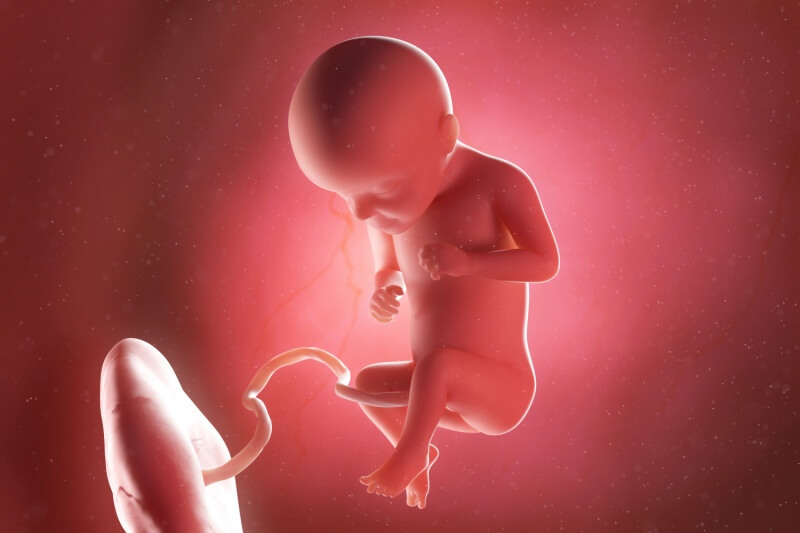

Your Baby at 29 Weeks of Pregnancy

At 29 weeks, your baby is roughly the size of a butternut squash, weighing around 1.2 kg.

Measuring about 26 cm from crown to rump and 38 cm in total length, your baby is beginning to run out of space in your womb.

This change in their environment influences both their movements and development.

Here’s what’s going on with your baby at 29 weeks of pregnancy:

- Maturing organs: While your baby’s organs are fully developed and functioning, the lungs remain an exception as they continue to mature in preparation for life outside the womb.

- Reproductive development: In boys, the testicles are migrating from the abdomen to the scrotum. In girls, the ovaries are now securely in the pelvis, and the labia are growing to cover the clitoris.

- Brain growth: Your baby’s brain is growing rapidly, allowing them to sense touch and pain. This development also helps them respond to their surroundings more acutely.

- Eye development: Pupils can now contract and dilate in response to light, which your baby can perceive through your stretched abdominal skin.

- Positioning: With limited space, your baby might curl into a foetal position, head near their knees.

- Movement: Kicks and movements are now more pronounced and might feel like sharp elbows nudging for space.

Each new development brings your baby closer to being ready for the world.

You may feel more and more connected to your little one as you sense these changes through their increasingly active movements.